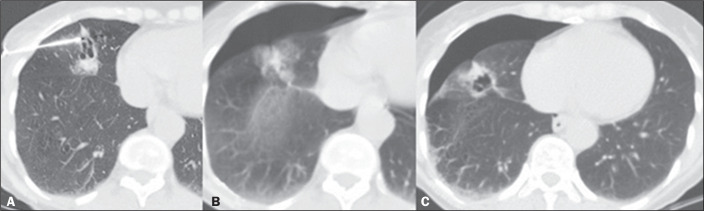

Objective: To assess the diagnostic success rate and complications of computed tomography (CT)-guided percutaneous biopsy in pulmonary nodules < 10 mm in diameter.

Materials and methods: This was a retrospective, single-center study involving the review of medical records, images, and chest CT reports related to 115 patients who underwent percutaneous CT-guided biopsy of < 10 mm pulmonary nodules between July 2015 and January 2019.

Results: Nodule diameter on the longest axis ranged from 4 mm to 9 mm, with a mean size of 7.7 mm. The mean age of the patients at the time of the procedure was 61 years, and 54.7% were women. Of the 115 nodules evaluated, 77 (67.0%) were solid and 55 (47.8%) were located in the lower lobes. The mean distance traversed by the needle in the lung parenchyma was 20 mm (range, 0-70 mm), and, in most cases, the biopsy was not performed with the patient in the biopsy-side-down lateral position. The diagnostic success rate was 93.0%. The most common complications were alveolar hemorrhage (in 36.5% of cases) and pneumothorax (in 24.3%).

Conclusion: The data suggest that CT-guided percutaneous biopsy of < 10 mm pulmonary nodules has a high diagnostic success rate and an acceptable rate of complications.